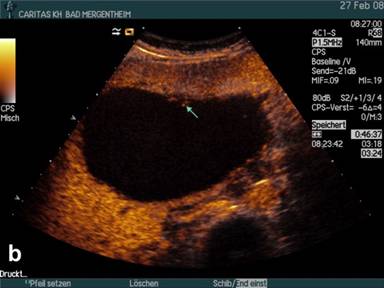

Seven patients with a history of chronic pancreatitis and actual pseudocysts in patients with pancreatitis revealed finally ductal adenocarcinoma of the pancreatic head (5 patients), corpus (1 patient), and tail (1 patient). The mean diameter of the lesions was 62±24 mm (range: 40-120 mm). All lesions showed arterial enhancement but less pronounced compared to the surrounding pancreatic parenchyma (Figure 2). Isolated macrovessels transversing the cyst(s) could not be visualised.

Figure 2. B-mode imaging (a.) and contrast enhanced ultrasound (CEUS) (b.) in a patient with a small partially cystic ductal adenocarcinoma in a patient with chronic pancreatitis proven by operation and histology. |